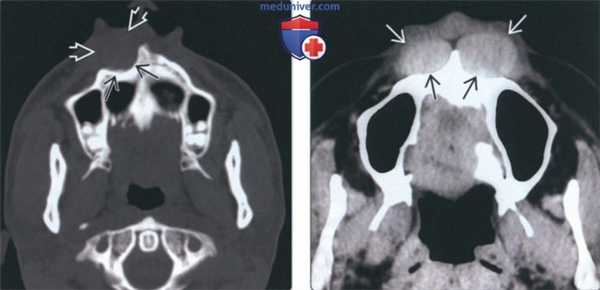

(Слева) При аксиальной КТ без контрастного усиления спереди от предчелюстной кости (с обеих сторон) визуализируются гиперденсные объемные образования округлой формы с четкими контурами. Образования вызвали выраженное ремоделирование верхней челюсти (больше слева). Носогубные кисты являются двухсторонними менее чем в 10% случаев.

(Слева) На аксиальной КТ в костном окне определяется ремоделирование передних отделов верхней челюсти справа, обусловленное односторонней носогубной кистой.

(Справа) На аксиальной КТ без КУ определяются хорошо отграниченные двухсторонние образования округлой формы возле передних отделов верхней челюсти, приводящие к легкому ее ремоделированию, больше выраженному слева. Двухсторонними являются